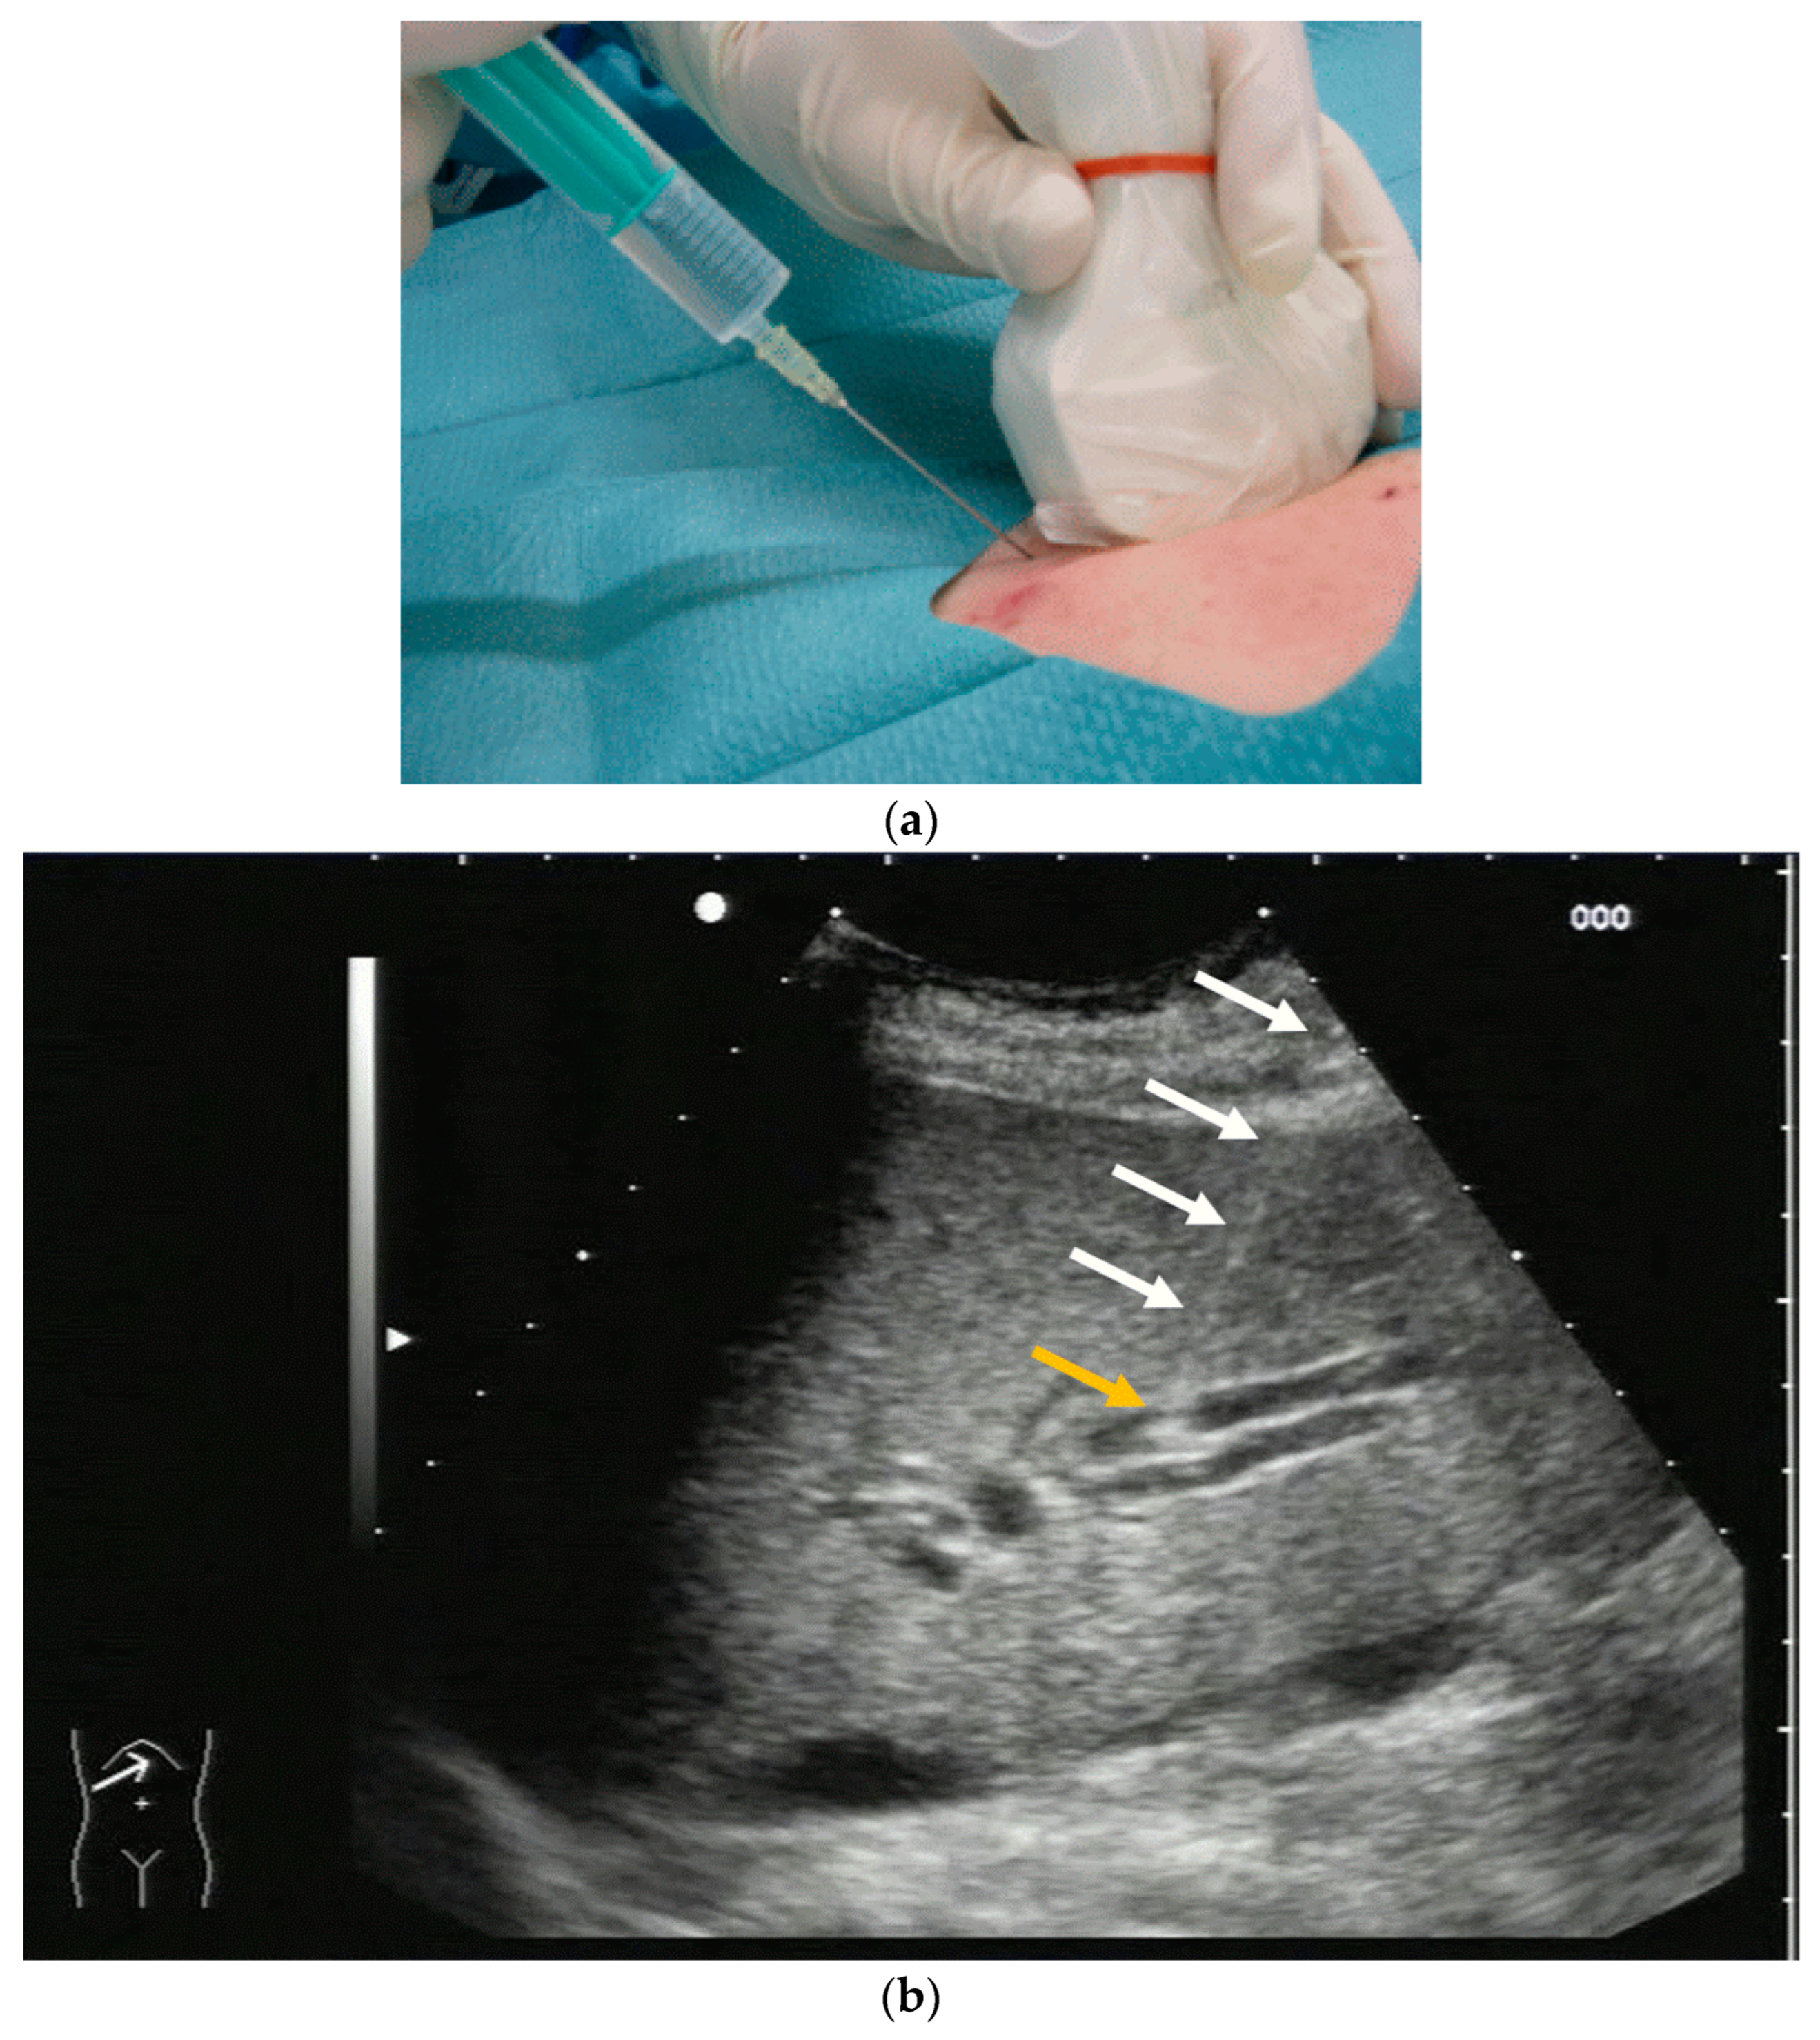

Again, the “in plane” approach is recommended to depict the needle in real time and continuously on its way. This is mandatory because iatrogenic perforation of the posterior gallbladder wall must be avoided. Both the drainage techniques, Seldinger (Figure 11a–c) and trocar (direct puncture, cf. Figure 10), may be used, depending on the physician’s preferences [43,58].

Figure 11.

When using the Seldinger technique, first a Chiba needle is placed in the gallbladder (a), through which a 0.035” guide wire with bended tip is inserted (b). Plastic pigtail drainage (c) is then advanced over the guide wire.

We recommend the use of 8F or 10F pigtail drainage. If it is inserted using Seldinger’s technique, dilatation is not necessary. If the guide wire is confirmed to be in the correct place and is secured well, drainage placement can be performed without US visualisation [43,76].

As tube displacement is a relevant problem, we recommend the use of thread-locked catheters, which are supposed to keep the pigtail in its curled shape, thereby preventing dislocation.